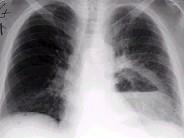

问题 男,36岁,胸痛半月伴发高热,胸片发现占位性病变,CT检查如图,最可能的诊断为 ( )

选项 A.左下肺肺脓肿 B.左下肺癌并空洞形成 C.左侧胸腔积脓 D.左下肺囊肿 E.左下肺肺炎

答案 A